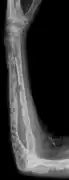

The diagnostic examination of a person with suspected multiple myeloma typically includes a skeletal survey. This is a series of X-rays of the skull, axial skeleton, and proximal long bones. Myeloma activity sometimes appears as "lytic lesions" (with local disappearance of normal bone due to resorption) or as "punched-out lesions" on the skull X-ray ("raindrop skull"). Lesions may also be sclerotic, which is seen as radiodense.[64] Overall, the radiodensity of myeloma is between −30 and 120 Hounsfield units (HU).[65] Magnetic resonance imaging is more sensitive than simple X-rays in the detection of lytic lesions, and may supersede a skeletal survey, especially when vertebral disease is suspected. Occasionally, a CT scan is performed to measure the size of soft-tissue plasmacytomas. Bone scans are typically not of any additional value in the workup of people with myeloma (no new bone formation; lytic lesions not well visualized on bone scan).

X-ray of the forearm, with lytic lesions